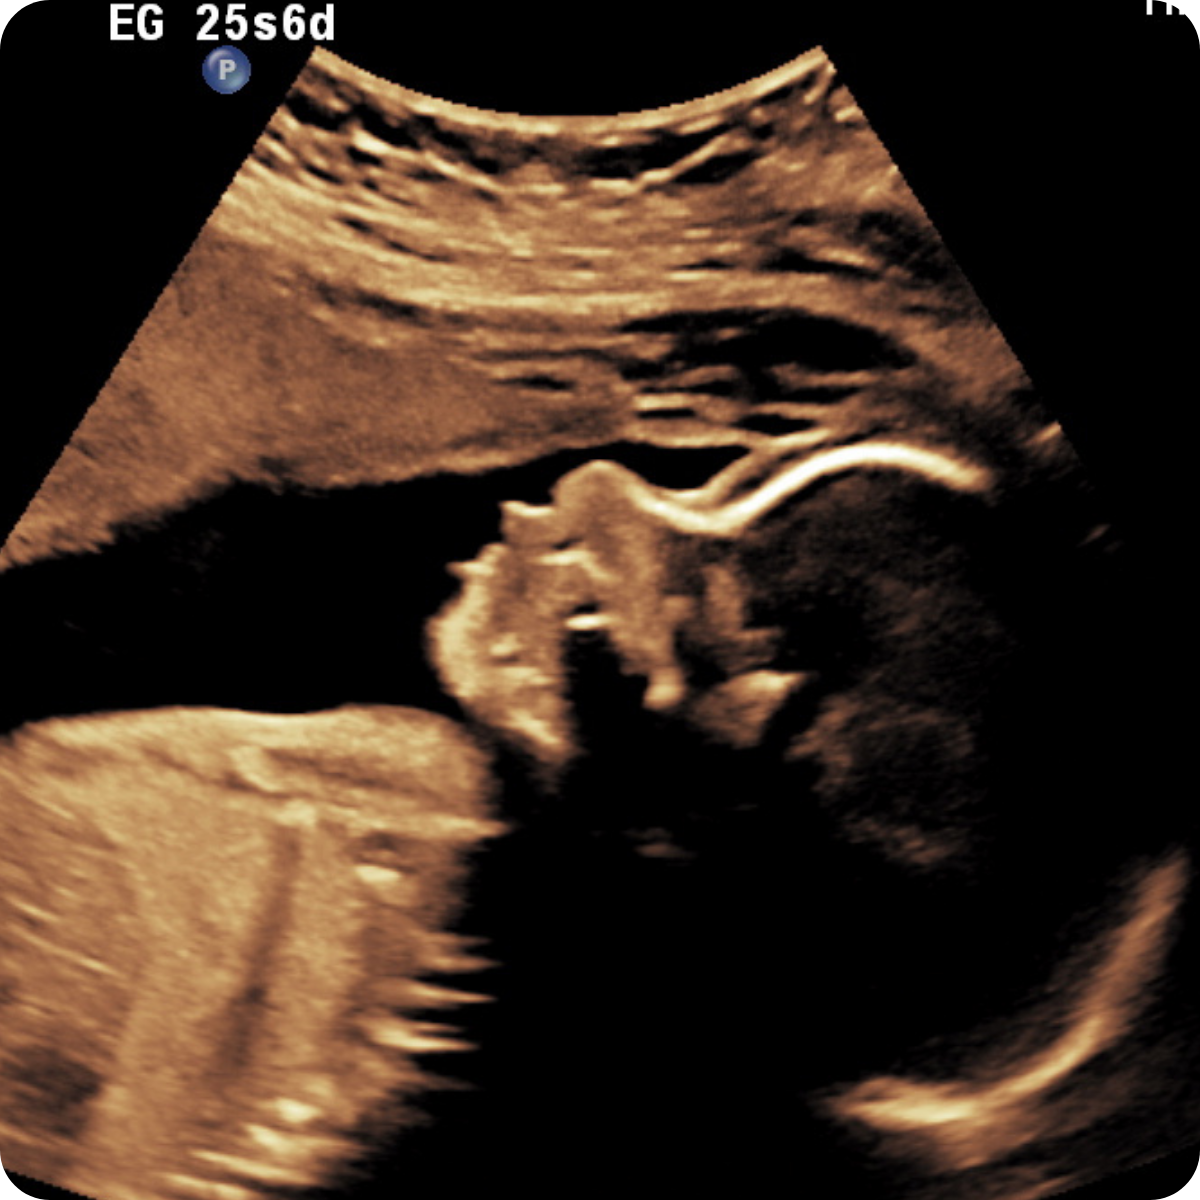

Realizarlo ideal entre las 20 a 24 semanas.

Una de las ecografías más importantes del embarazo. Este es el momento para descartar anomalías fetales de órganos, sistemas y evaluar la circulación placentaria.